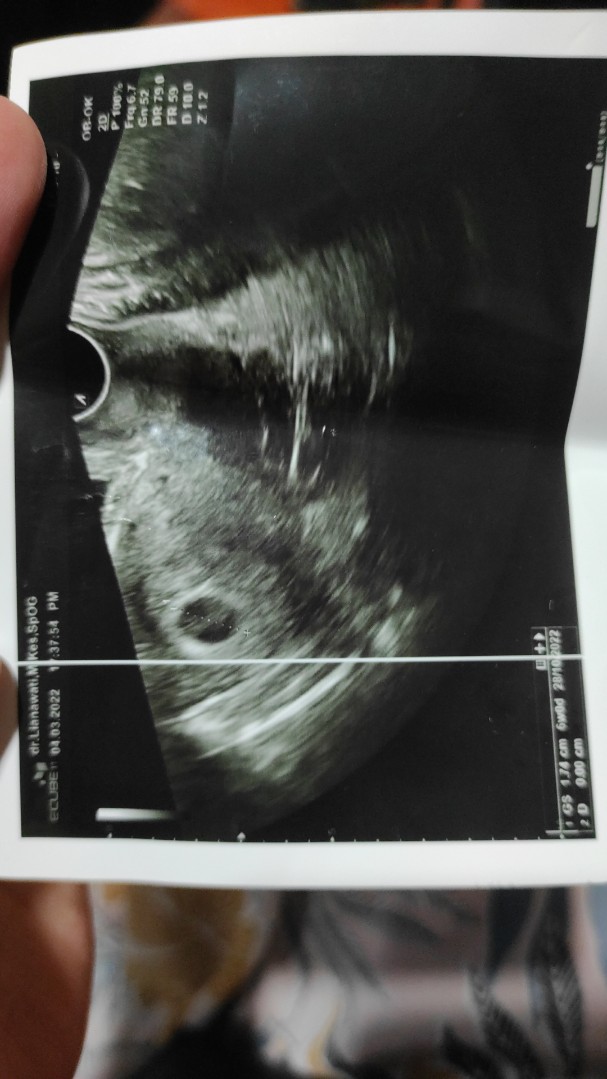

amiin...kmrn q ke dokter diUSg blm keliatan janin,di usg transvaginal jg blm keliatan janin.hanya tampak kantung kehamilan.normalkah bund?q disuruh dtg 2 mggu lg.kt dokter diliat janinnya berkembang apa tdk...jd takut😢 semoga sj berkembang yah bund😢🥲

btw bunda udah USG blm? Minggu lalu aku USG transvaginal tp ktanya msh penebalan dinding rahim